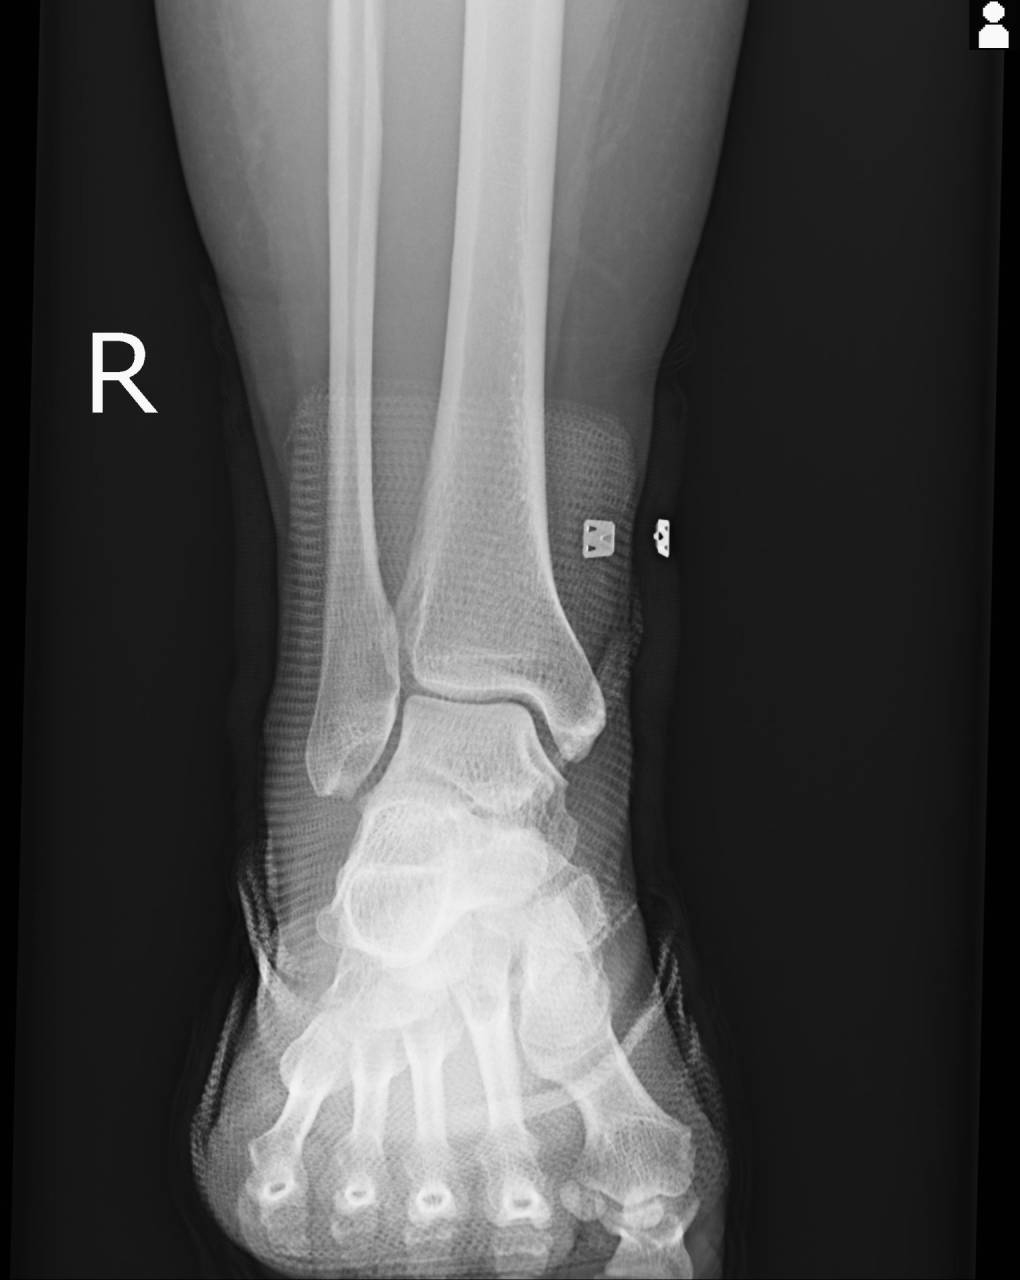

骨折の疑いがあったので当整骨院が提携している病院にてレントゲン検査を依頼し、撮影した画像を確認すると触診で圧痛のあった前距腓靭帯付着部の腓骨部とエコー画像では鮮明でなかった前距腓靭帯付着部の腓骨部より1cm上の部分に骨折があったとのことで骨折として施術を進めていきます。